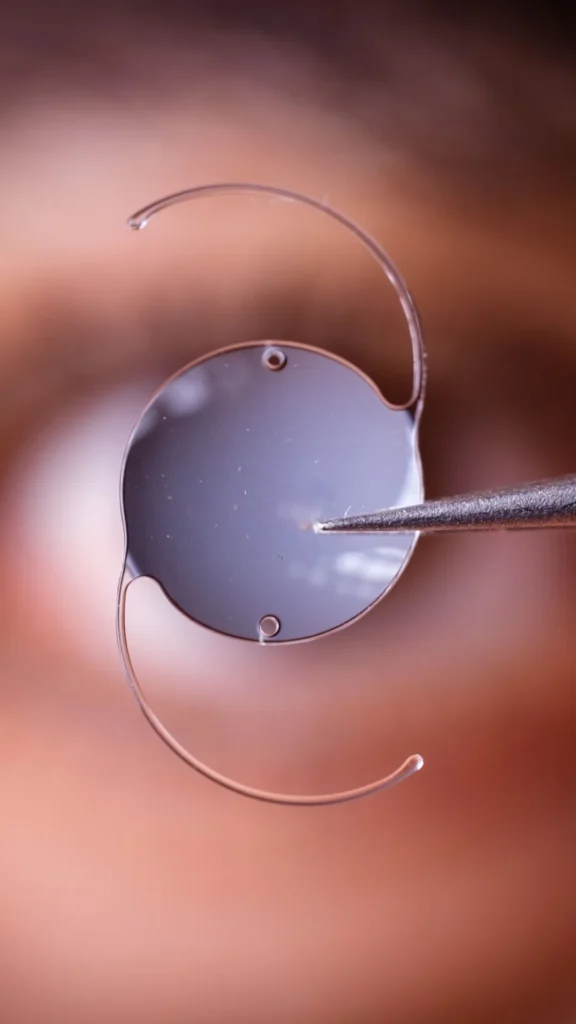

Estou aqui para ajudar a transformar essa realidade. Com a cirurgia de catarata, podemos restaurar a clareza da sua visão utilizando lentes intraoculares tecnológicas de última geração. Essas lentes são projetadas para melhorar significativamente sua qualidade de vida, proporcionando conforto e segurança.

A cirurgia de catarata é um procedimento moderno e seguro onde o cristalino opaco do olho é removido e substituído por uma lente intraocular. Cada tipo de lente tem suas vantagens e pode ser escolhido com base nas necessidades e estilo de vida do paciente. Conversar com um oftalmologista é fundamental para decidir qual opção de lente é a melhor para cada caso. Esta intervenção é rápida e realizada com anestesia local, garantindo conforto e segurança ao paciente.

Essas lentes são projetadas para corrigir a visão em uma única distância, geralmente a visão de longe. Após a cirurgia, pode ser necessário usar óculos para leitura ou para distâncias intermediárias.

Estas lentes oferecem correção para múltiplas distâncias, incluindo perto, intermediário e longe, proporcionando uma visão mais completa sem a necessidade de óculos.

Especialmente projetadas para corrigir o astigmatismo, além de melhorar a visão de longe ou de perto. Indicadas para pacientes com astigmatismo, proporcionando uma visão mais clara e focada.

Lentes EDOF (Extended Depth of Focus)

Estas lentes aumentam a profundidade de foco, oferecendo uma visão mais nítida em uma gama de distâncias, especialmente intermediárias e de longe. Ideais para pessoas que precisam de boa visão a média distância, como para usar o computador.